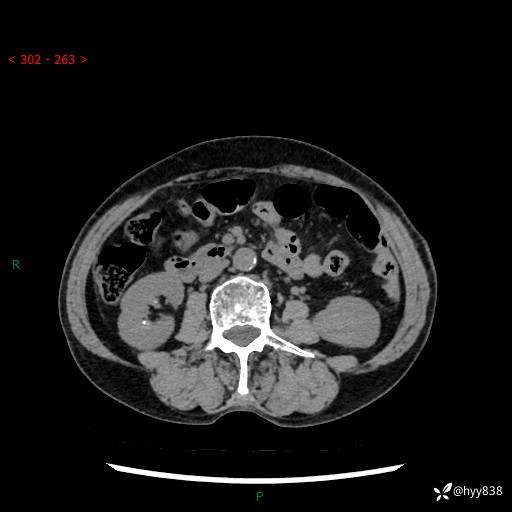

72岁/女,检查发现左肾占位1天。为了满足诊断,常规四期后,又加了延迟期-结果公布~

【患者信息】:72岁/女

【主诉】:检查发现左肾占位1天

【现病史及既往史】:患者于1天前检查发现左肾占位,无畏寒发热,无咳嗽咳痰,无腰腹部疼痛不适,无肉眼血尿、无尿频尿急症状,起病来,患者未行特殊治疗,为求进一步诊治,门诊以"左肾占位"收治入院。 发病来患者精神、饮食、睡眠良好,小便如上,大便正常,体重无明显变化。

【检查】:肾脏CT平扫+增强